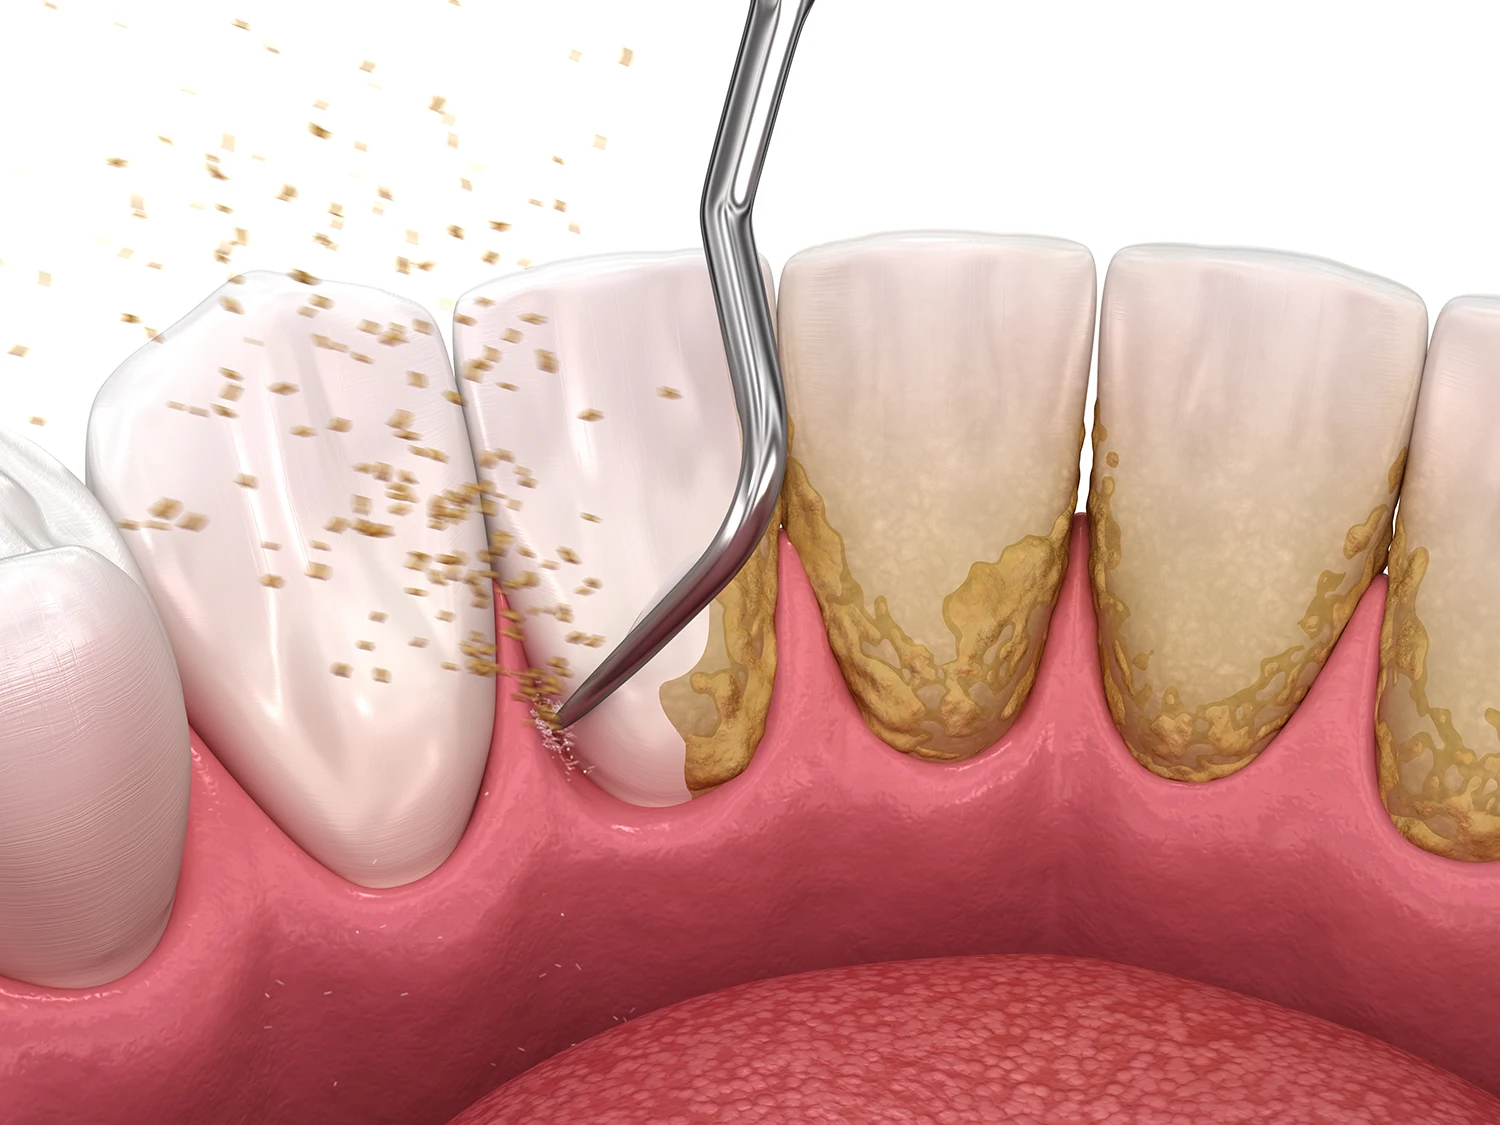

È un trattamento eseguito da un igienista dentale che rimuove placca e tartaro dalle superfici dentali e sotto il margine gengivale. Anche con una buona igiene quotidiana, alcune zone restano difficili da raggiungere con spazzolino e filo interdentale.

Durante la seduta si utilizzano strumenti ad ultrasuoni e manuali per eliminare il tartaro, seguiti da una lucidatura finale che rende i denti più lisci e meno soggetti all’accumulo di batteri.